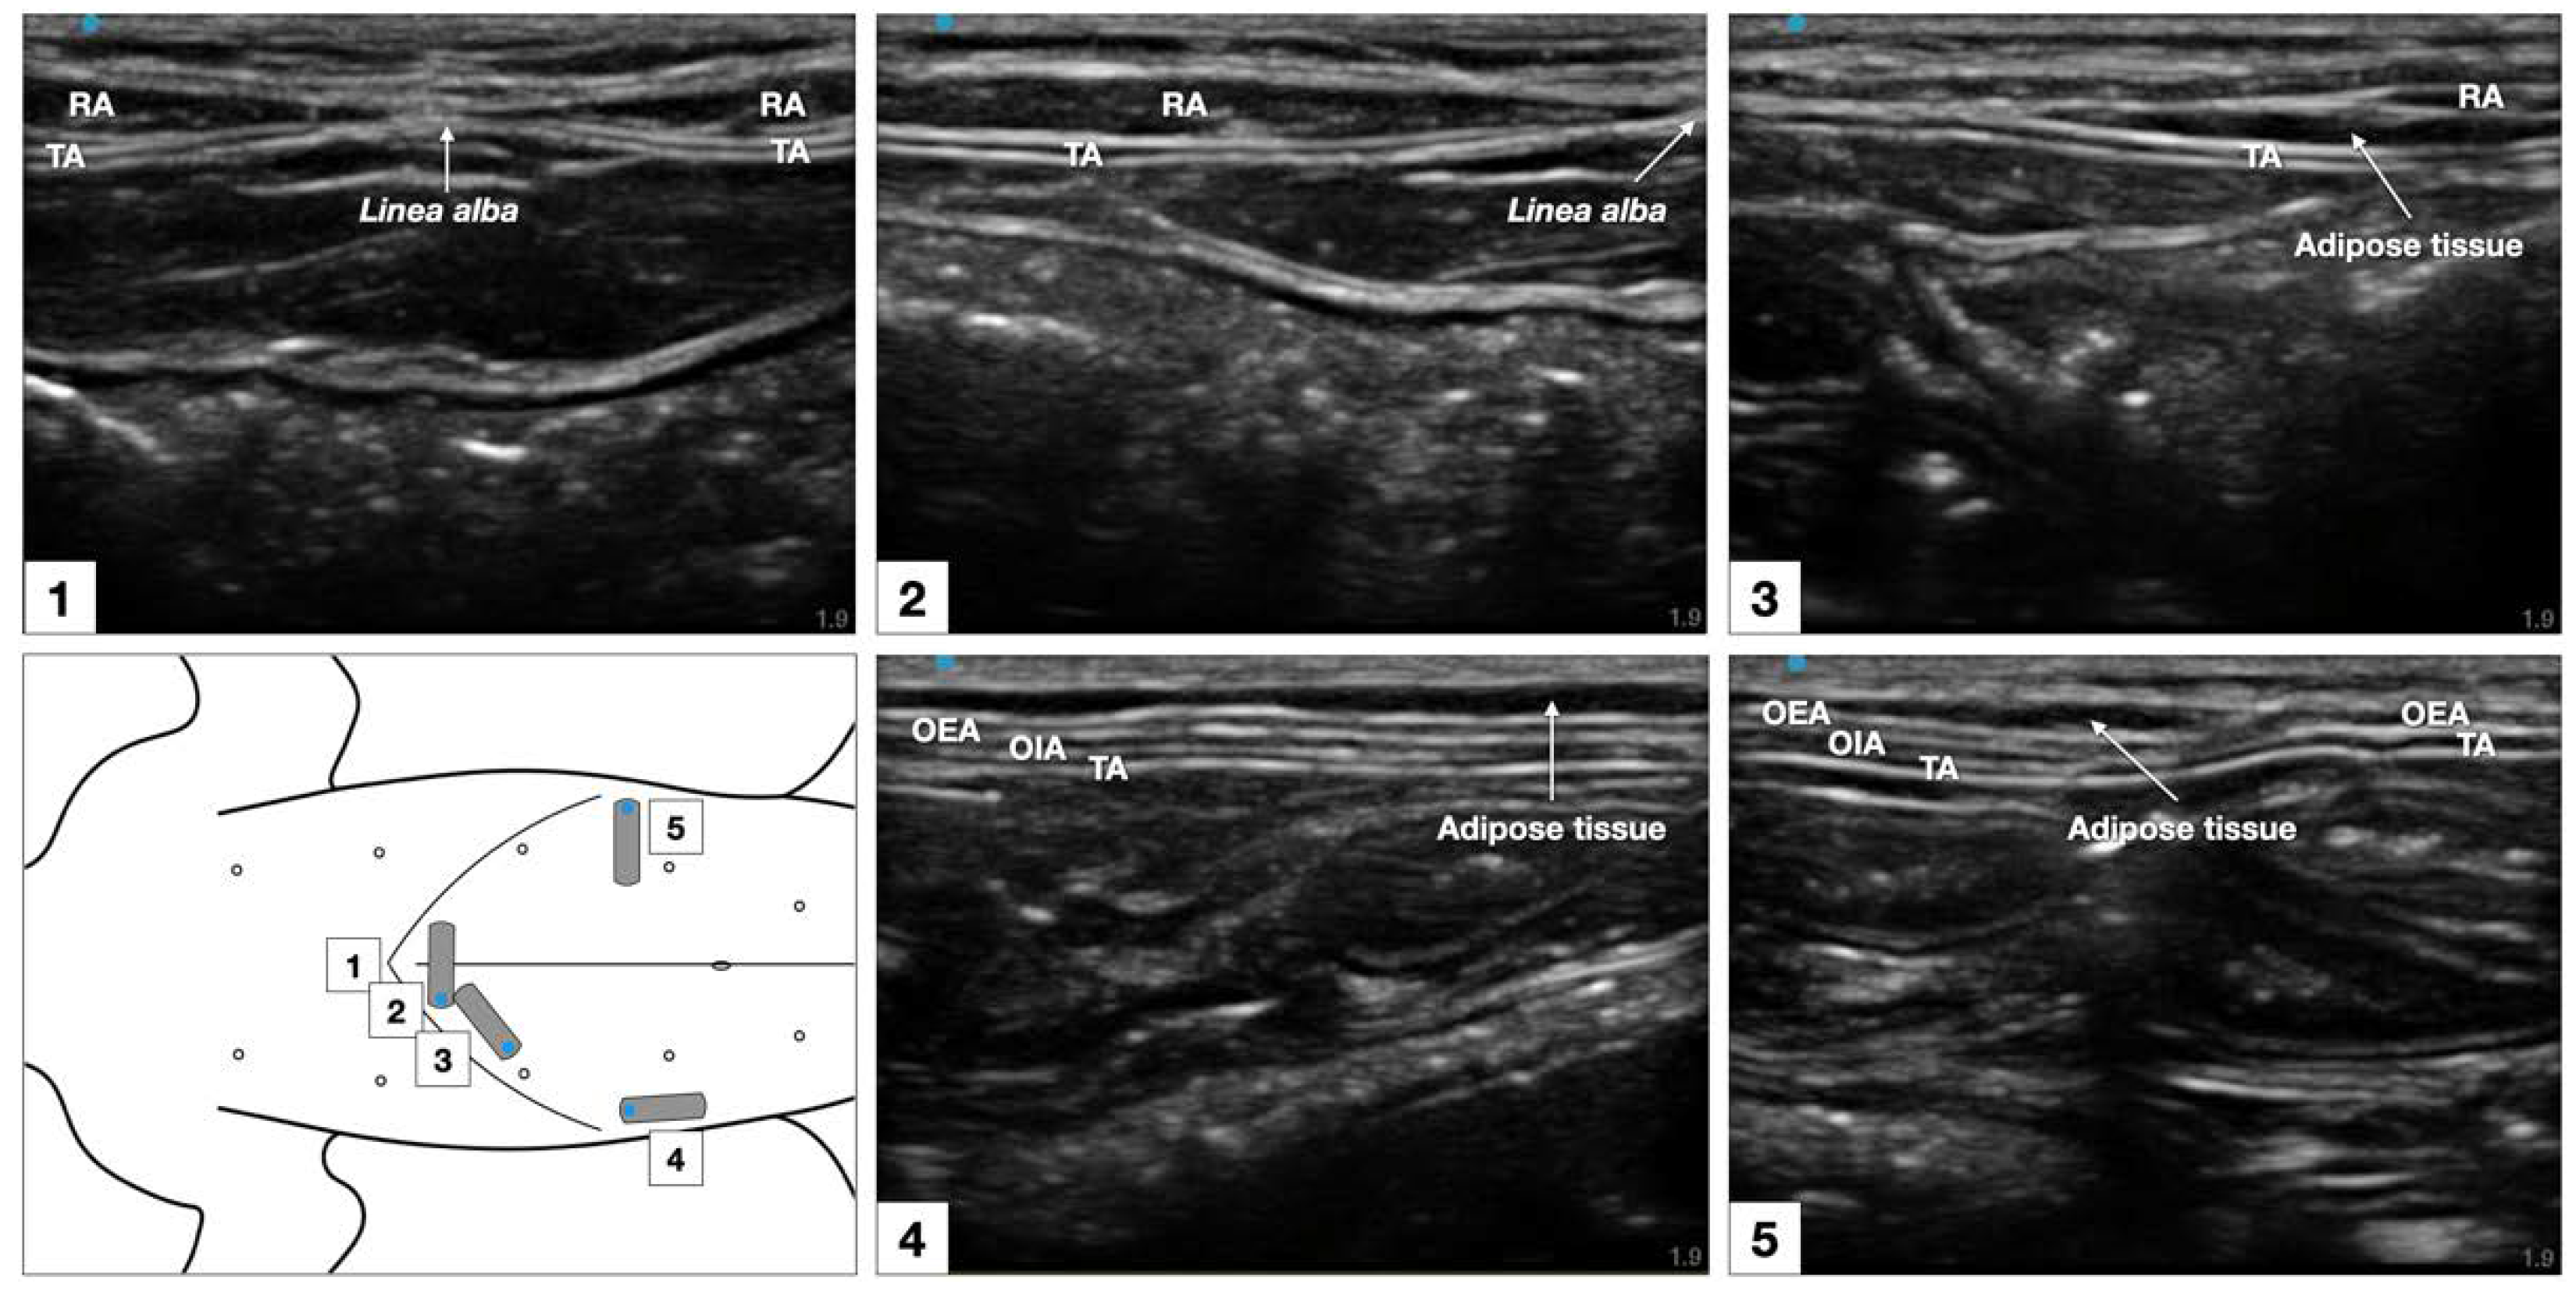

The sonographic appearance of the TAP varied depending on the position of the US transducer and is shown in Figure 6.

Figure 6. Sonographic identification of the TAP in a cat cadaver. At the subcostal region, the m. transversus abdominis (TA) was visualized as the more hypoechoic muscle layer just beneath the m. rectus abdominis (RA), and the TAP was discerned as a hyperechoic line between the two muscles. At the lateral region of the abdomen (at mid-level between axilla and iliac crest, and lateral to the mammary gland line), three hypoechoic layers were observed, corresponding to m. transversus abdominis, m. obliquus internus abdominis (OIA) and obliquus externus abdominis (OEA) from a deep to superficial order. The TAP was identified as a hyperechoic line superficial to the m. transversus abdominis. At the abdominal level, 1–3 cm lateral to the ventral midline (between the lateral margin of the m. rectus abdominis and the medial margin of the m. obliquus internus abdominis) the TAP and the aponeurosis of the m. obliquus internus abdominis appeared as a unique tick hyperechoic line.